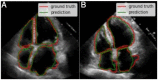

Cardiovascular diseases related to the right side of the heart, such as Pulmonary Hypertension, are some of the leading causes of death among the Mexican (and worldwide) population. To avoid invasive techniques such as catheterizing the heart, improving the segmenting performance of medical echocardiographic systems can be an option to early detect diseases related to the right-side of the heart. While current medical imaging systems perform well segmenting automatically the left side of the heart, they typically struggle segmenting the right-side cavities. This paper presents a robust cardiac segmentation algorithm based on the popular U-NET architecture capable of accurately segmenting the four cavities with a reduced training dataset. Moreover, we propose two additional steps to improve the quality of the results in our machine learning model, 1) a segmentation algorithm capable of accurately detecting cone shapes (as it has been trained and refined with multiple data sources) and 2) a post-processing step which refines the shape and contours of the segmentation based on heuristics provided by the clinicians. Our results demonstrate that the proposed techniques achieve segmentation accuracy comparable to state-of-the-art methods in datasets commonly used for this practice, as well as in datasets compiled by our medical team. Furthermore, we tested the validity of the post-processing correction step within the same sequence of images and demonstrated its consistency with manual segmentations performed by clinicians.